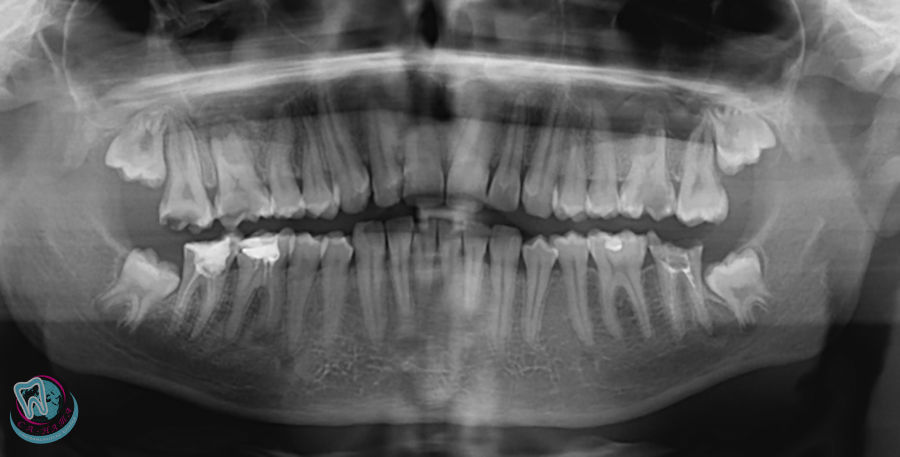

During the initial dental examination, the dentist can see only half of the tooth — the crown and part of the tooth root — while the rest remains hidden. To obtain a complete picture, an X-ray is required. Before treating a serious dental condition, a panoramic X-ray is performed to provide a detailed view of the entire dentition and identify potential issues.

It helps to determine:

Contact between teeth not visible during a visual examination;

Root caries;

Cysts or bone formations;

Teeth that have not yet erupted and primary teeth;

Granulomas and the condition of the sinuses.